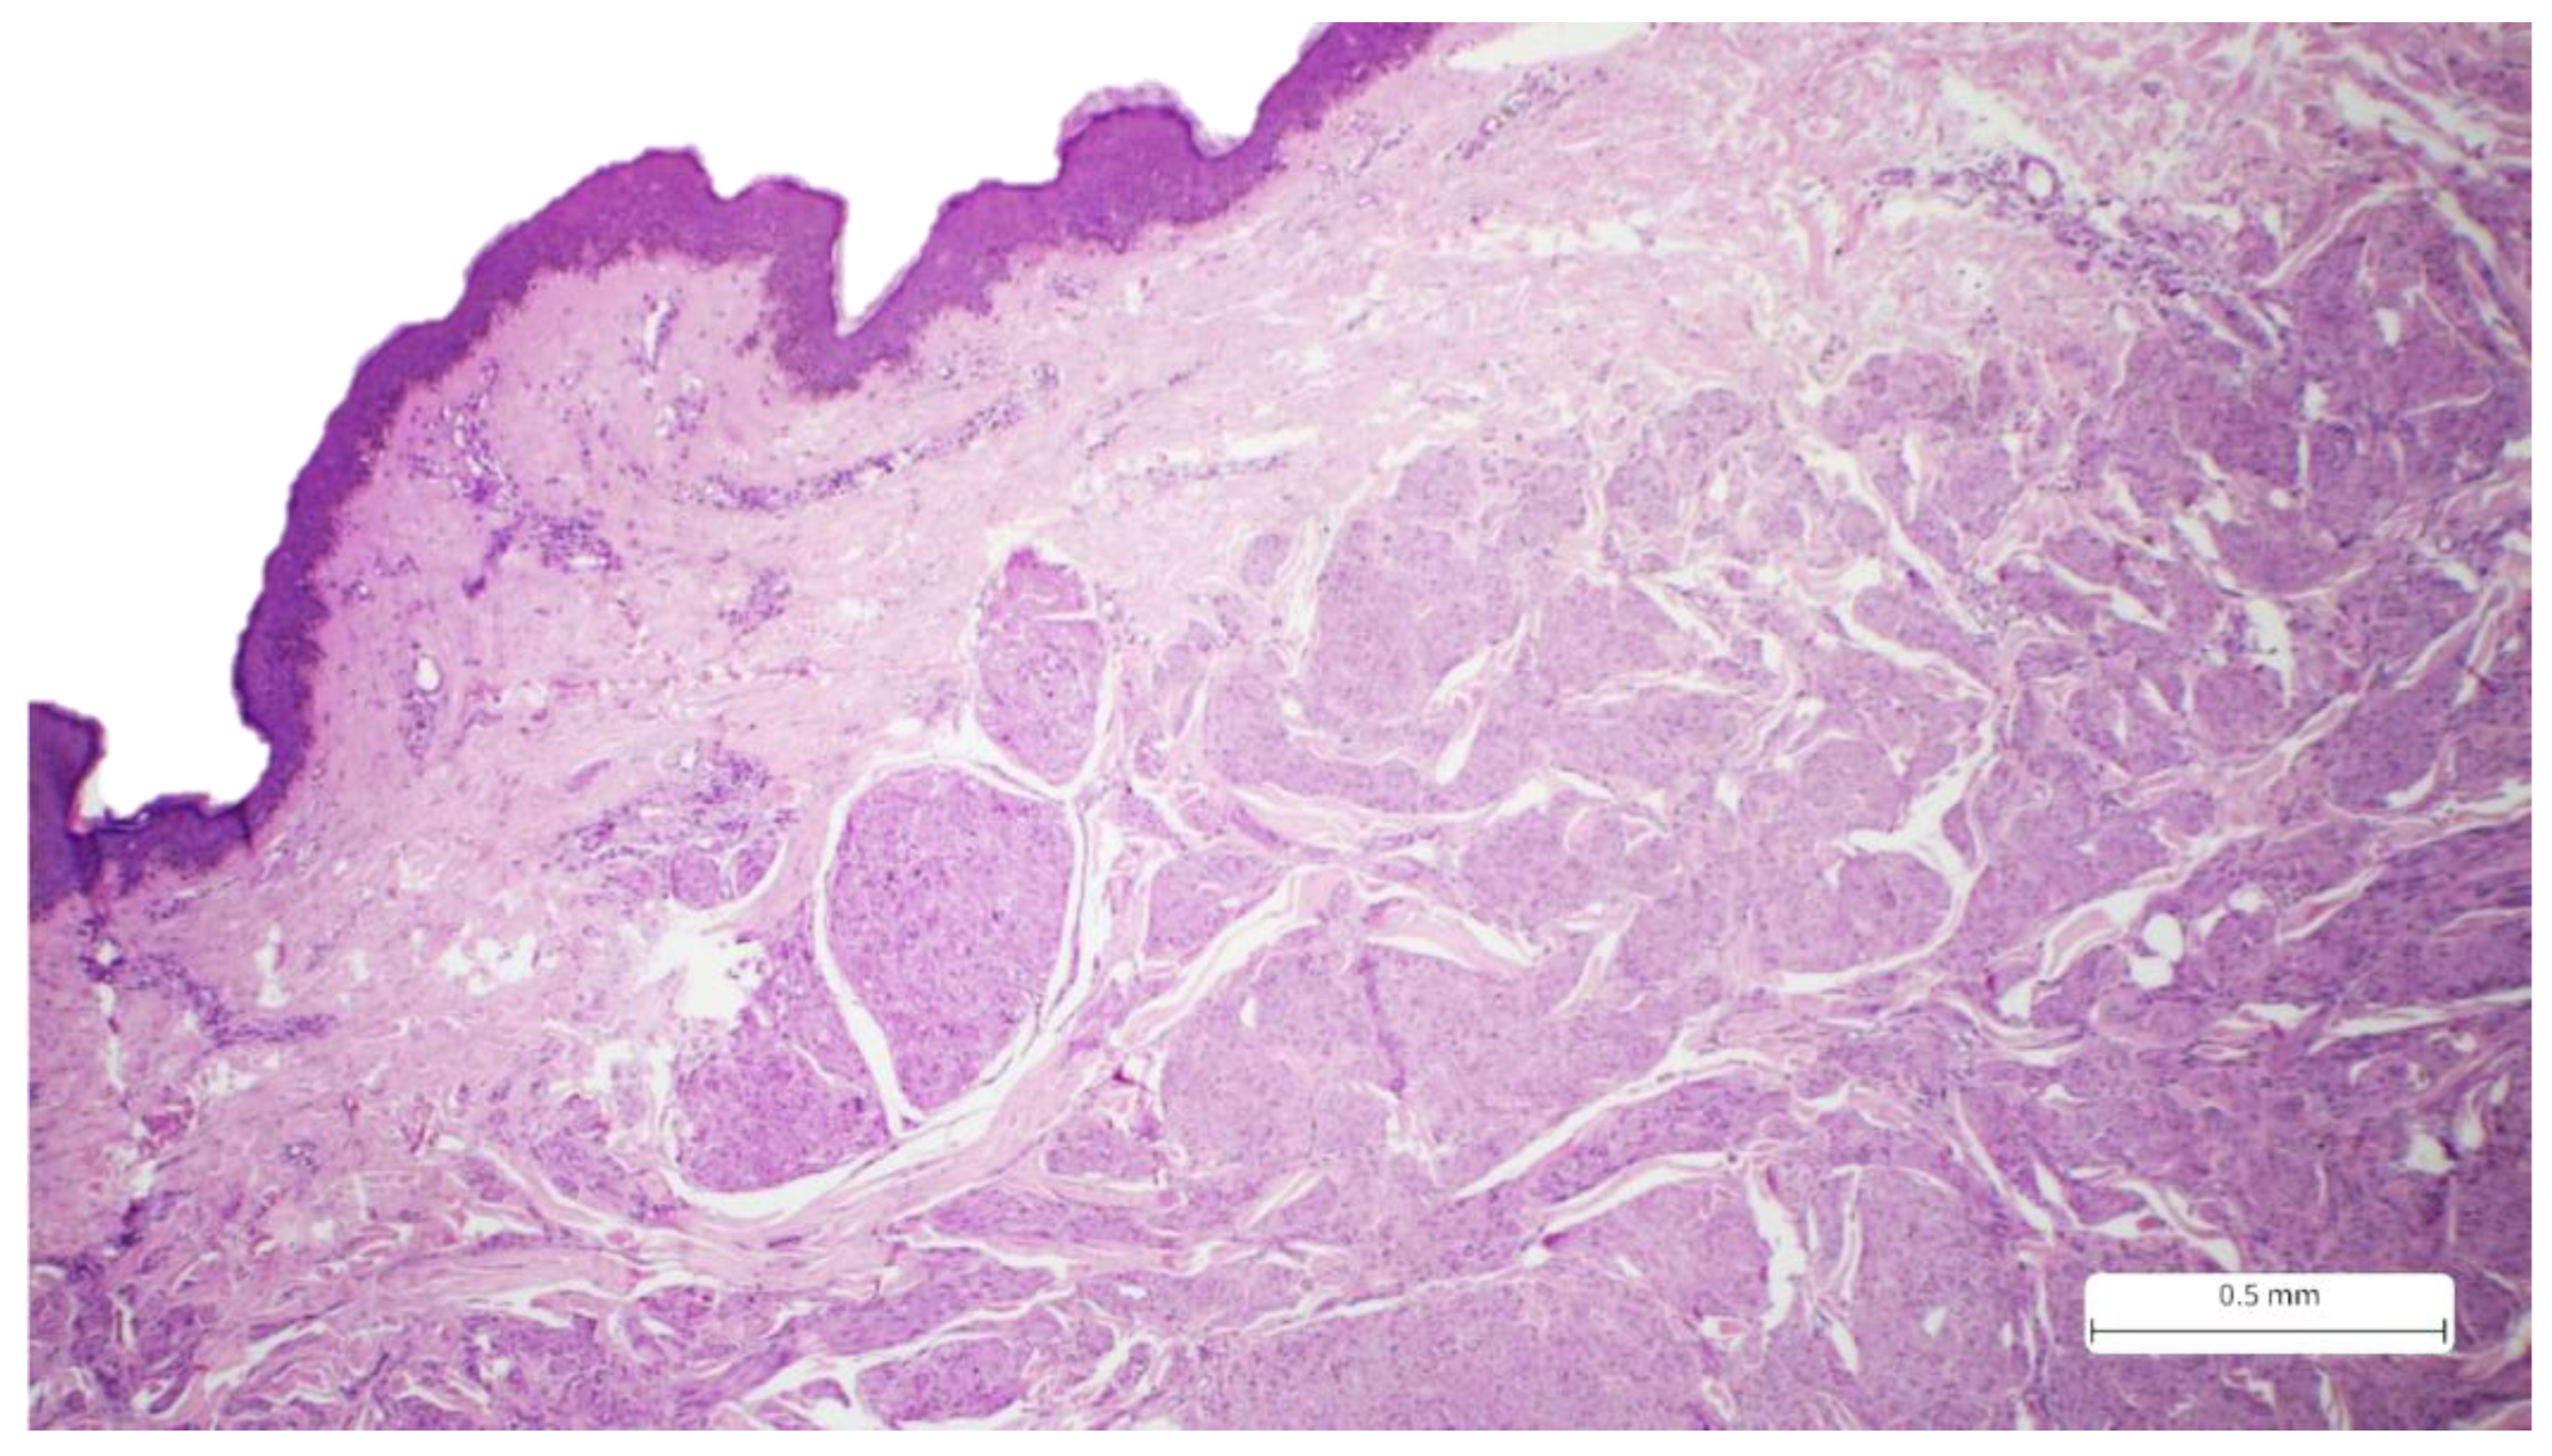

Figure 1. Cutaneous sample covered by stratified squamous epithelium, which presents a tumor proliferation with an infiltrative pattern and irregular borders in the reticular dermis, Hematoxylin-eosin.

The initial excision (September 2021) consisted of a cutaneous sample measuring 36 x 10 mm, with a thickness of 25 mm, and presented a firm, white area of 30 x 9x 24 mm on the cut section. Histological analysis using the usual Hematoxylin-eosin staining revealed a solid tumor proliferation in the reticular dermis. The tumor was composed of fascicles of spindle cells with visible storiform areas. The tumor cells showed eosinophilic cytoplasm, elongated and enlarged nuclei with irregular borders, and a cigar-shaped appearance. Some cells exhibited high pleomorphism, with hyperchromatic and lobulated nuclei. The mitotic index was 15/10 HPF. Necrosis and lymphatic or vascular invasion were not identified. The tumor infiltrated the deep surgical resection margin.

Microscopic examination of the tumor samples provides crucial data for the patient’s prognosis. On the HE stains, we can observe details regarding the tumor's architecture and cytology. Typically, LMS presents solid proliferation, with tumor cells arranged in fascicles with storiform patterns. The cells are spindle-shaped, with eosinophilic cytoplasm and elongated nuclei that have a cigar-shaped appearance. Pleomorphism and atypia are evident, and the mitotic count is commonly high [1,15]. Despite these characteristics, HE staining alone is insufficient for diagnosis, as LMS can exhibit variability in these features and resemble other sarcomas with similar patterns (for example, tumors of neural or melanocytic origin). Thus, confirmation of the diagnosis is required, and immunohistochemistry is performed. Markers such as SMA (smooth muscle actin), desmin, and caldesmon are used to determine the myogenic origin. The tumor should be positive for at least two of these markers. Our case showed positivity for SMA and desmin. Caldesmon was not performed due to limited availability in our laboratory. Additionally, the Ki-67 proliferation index was expressed in 30% of the tumor cells. Neural origin (malignant peripheral nerve sheath tumor) and melanocytic origin (spindle cell melanoma) were excluded based on IHC, not only due to positivity for myogenic markers but also due to negativity for S100. For spindle cell melanoma, markers like PRAME and SOX10 would exhibit higher specificity, but S100 is highly sensitive for melanocytic lineage. Atypical fibroxanthoma (AFX), a key differential diagnosis of LMS, was also excluded because the CD68 marker was negative. AFX also presents additional details such as the presence of epithelioid or multinucleated cells, which were absent in our case. Other spindle cell tumors, such as dermatofibrosarcoma protuberans (DFSP), also enter the differential diagnosis. However, this neoplasm typically exhibits a storiform pattern with invasion of the hypodermis, a classic aspect known as “honeycomb”, a feature which is absent in the usual stain in our case. In addition, the mitotic index is low, and the tumor exhibits CD34 positivity. The CD34 marker is essential for DFSP diagnosis and differential diagnoses with storiform tumors, and its positivity excludes LMS [16,17,18,19,20,21].